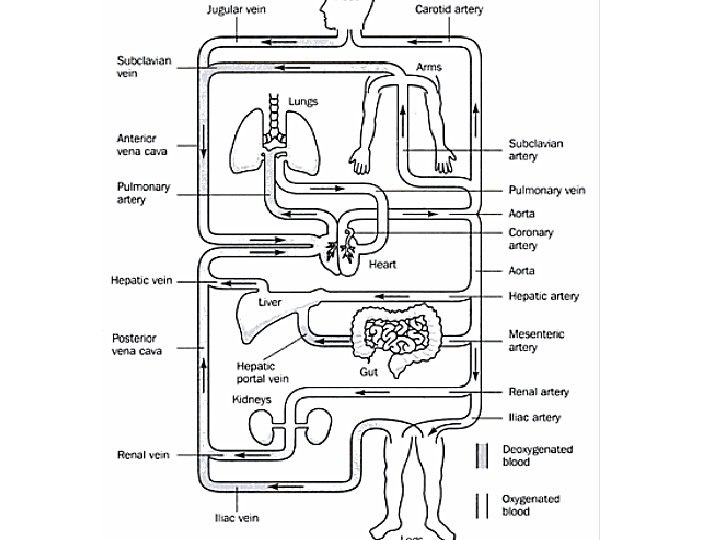

Circulation Summary • Consists of heart, blood and blood vessels • Double-circulation as blood travels twice through heart in one journey • Pulmonary circulation (heart lungs) • Systemic circulation (Heart body) • Oxygenated (O 2 rich) heart to body • Deoxygenated (O 2 poor) body to heart

Path of Oxygenated Blood • Pulmonary vein left atrium • Through mitral valve down into the left ventricle. • The ventricle then contracts forcing the mitral valve closed and opening the semilunar valve. • The blood then flows up into the aorta and around the body.

Path of Deoxygenated blood • Vena cava right atrium • Through tricuspid valve right ventricle. • Ventricle contracts, tricuspid valve closes, semilunar valve opens. • Blood flows to the pulmonary artery lungs.

ARTERIES vs. VEINS • All arteries carry blood AWAY from the heart. • Most arteries carry oxygenated blood. • Arteries have very thick external and muscular walls. • Arteries have small lumen with smooth interior walls. • All veins carry blood TO the heart. • Most veins carry deoxygenated blood. • have fairly thin external and muscular walls. • Veins have wide lumen with smooth interior walls and VALVES.

HEPATIC VEIN AND HEPATIC PORTAL VEIN • There is no mesenteric artery, because it would be a waste of time and nutrients if digested food were to go back directly to the heart without being filtered by the liver. • Therefore, deoxygenated blood from the gut goes to the kidney by a special vein called the hepatic portal vein. • Afterwards, the hepatic vein carries the filtered blood back the heart.